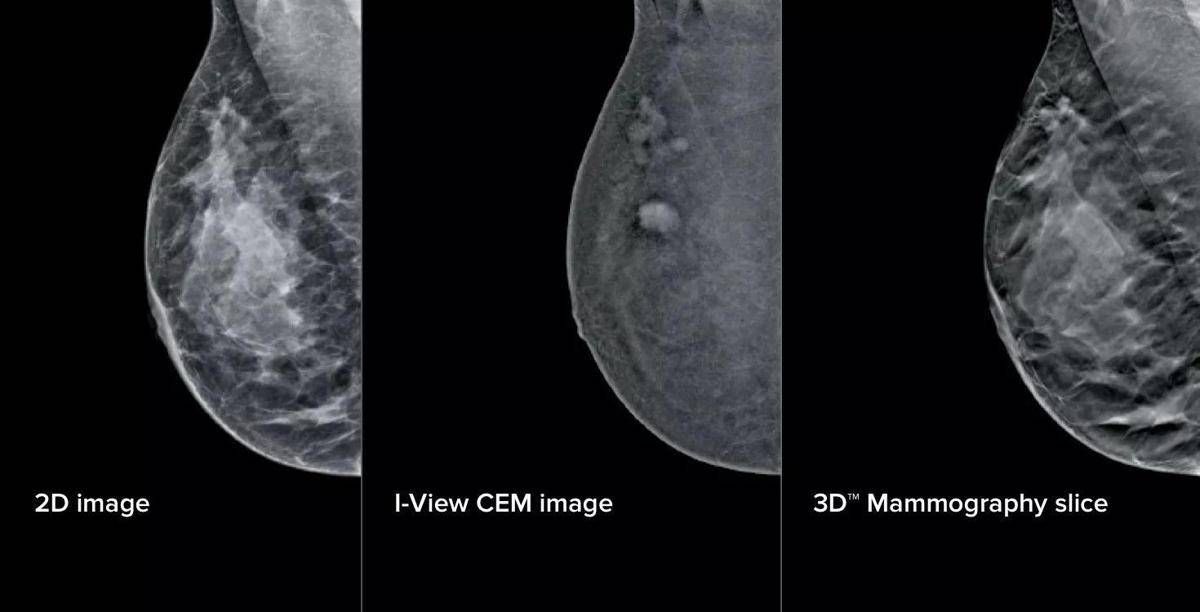

L’aggiornamento – illustra il San Camillo – si compone di elementi fisici e virtuali in due ambiti principali: la mammografia con refertazione e la biopsia mammaria. Sul fronte della refertazione, è stata introdotta una nuova workstation con monitor ad altissima risoluzione e strumenti avanzati di analisi delle immagini. Un software dedicato consente di valutare in modo oggettivo la densità del tessuto mammario, un elemento importante perché associato al rischio di tumore al seno. A questo si aggiunge un software che analizza struttura e densità del tessuto mammario, tecnologia di tomosintesi avanzata che riduce del 66% il numero di slice – le ‘fettine’ spesse 1 mm di tessuto mammario acquisite dal mammografo – mantenendo le stesse informazioni diagnostiche. Meno immagini da scorrere significa meno affaticamento: una riduzione del carico cognitivo per il radiologo stimata intorno al 13%, con benefici concreti soprattutto nelle sessioni di lettura multipla. A supporto dei medici – prosegue la nota – è stato integrato anche un sistema di intelligenza artificiale che evidenzia automaticamente le aree sospette sulle singole slice, come microcalcificazioni o alterazioni del tessuto, e fornisce indicazioni utili per la priorità di lettura. Studi preliminari indicano “un miglioramento della capacità di individuare lesioni fino al 9%”.

Sul fronte della biopsia mammaria, i mammografi di ultima generazione consentono di eseguire la procedura direttamente a partire da immagini con contrasto, unendo in un unico passaggio la localizzazione della lesione e il prelievo bioptico. Per la paziente questo si traduce in un percorso interamente nello stesso reparto, senza la necessità di ricorrere alla risonanza magnetica chiusa. Un apposito dispositivo meccanico permette inoltre di raggiungere anche le lesioni in posizioni difficili.